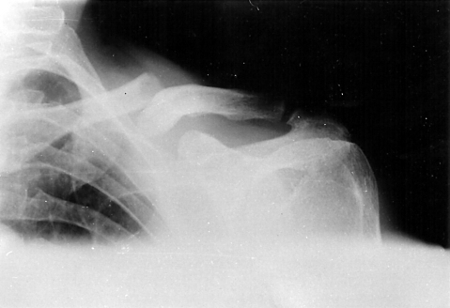

Clavicle fracture

Anteroposterior radiograph of left shoulder demonstrating a clavicle fracture

Alao D et al. Emergency Medicine Journal 2005;22:232-3; used with permission